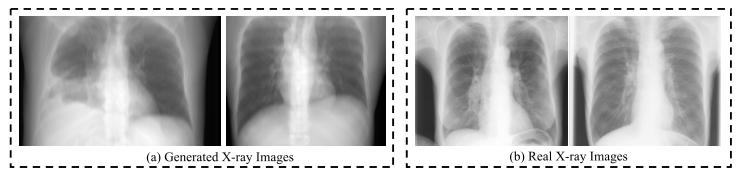

Fig. 4. Visualization of generated X-ray images from CT volumes of theDeepLesion dataset and real X-ray images from the JSRT dataset [67],[68]. Although blurrier than real ones, generated X-ray images still provideimportant anatomical information.

图4 DeepLesion数据集CT体积生成的X射线图像与JSRT数据集[67]、[68]中真实X射线图像的可视化对比 尽管生成的X射线图像比真实图像更模糊,但仍能提供重要的解剖学信息。